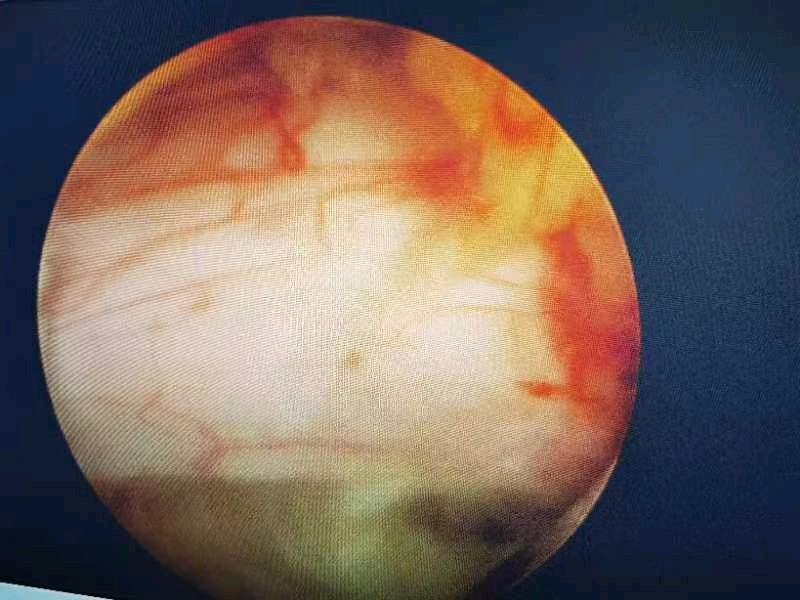

看着椎管内自由的神经根,心情是愉悦的,患者的心情更加愉悦,因为没有了那种钻心的疼痛!